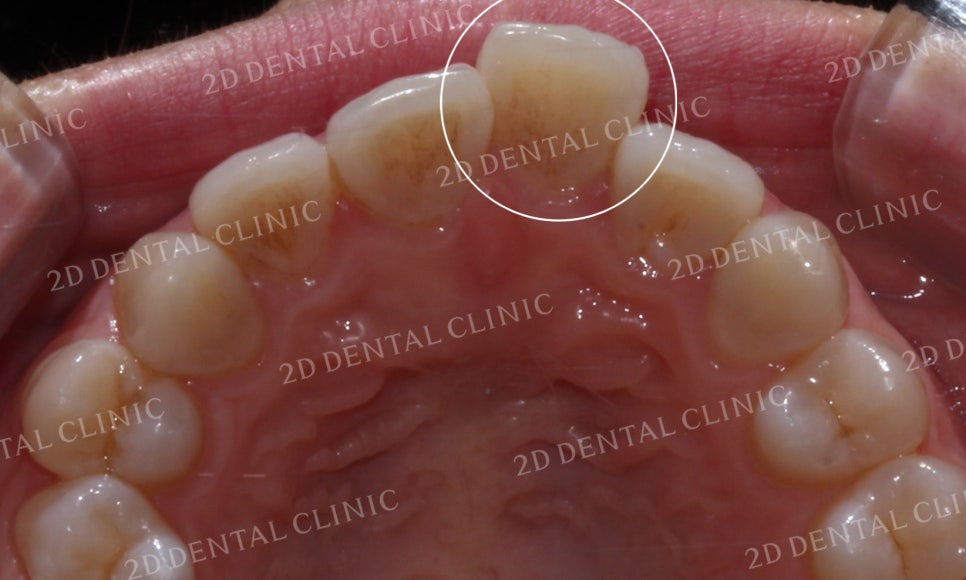

"덧니치아 교정 전"

덧니치아 투디교정 전

[투디교정] 덧니교정, 앞니교정으로 치열을 고르게! by.투디치과(2D치과)

상악의 안쪽면 사진에서도

중절치의 덧니 증상을 확인할 수 있습니다.